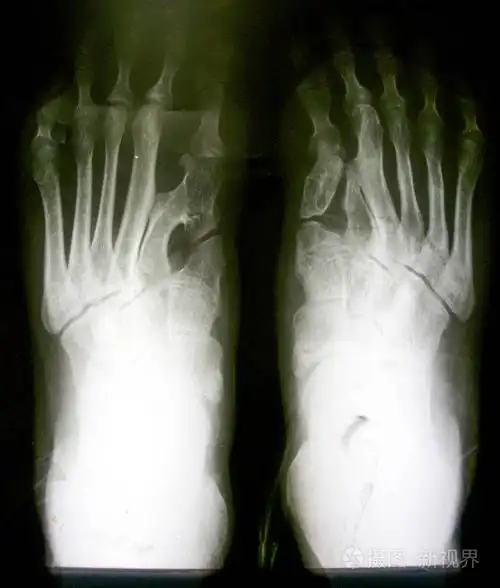

正常脚的 x 射线图像两个 sid

上海健桥医院拇外翻侯明主任正常脚型和拇外翻对比